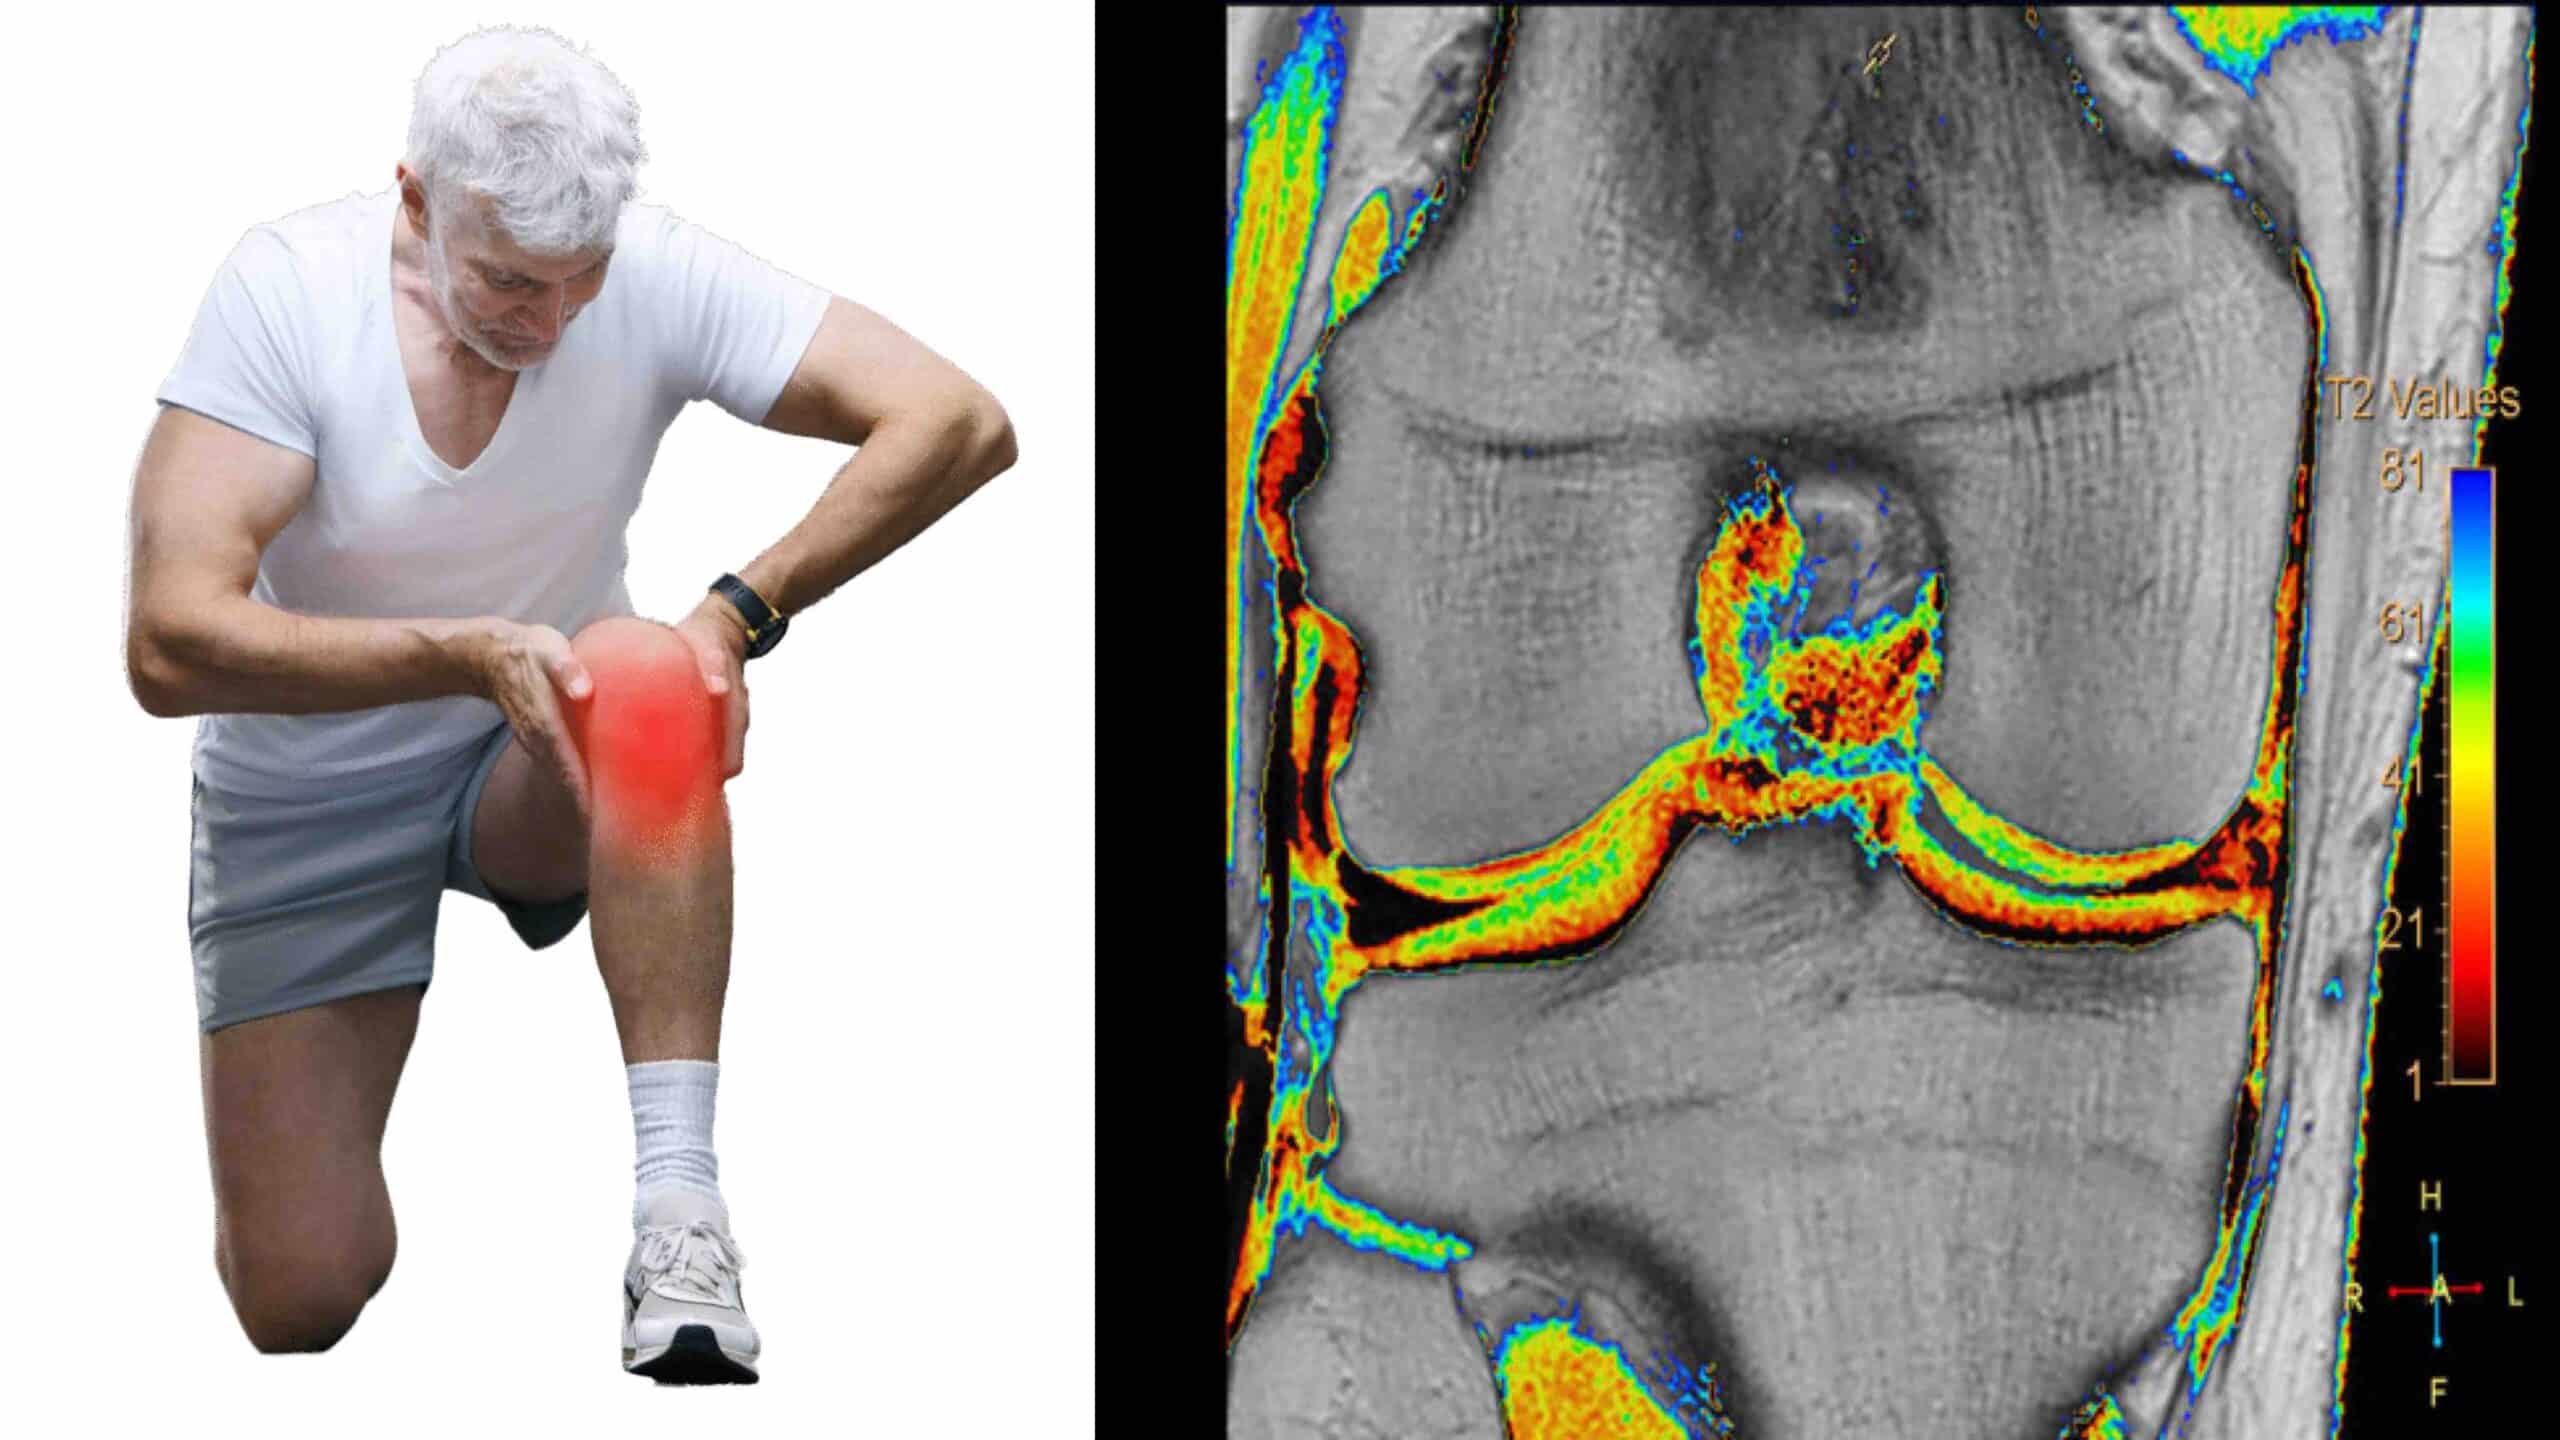

O método mais utilizado para se fazer a condrometria do joelho é através do exame de ressonância magnética. Essa técnica é também conhecida como ressonância condral. Sequências específicas do exame de ressonância magnética mapeiam a cartilagem do joelho e detectam alterações estruturais microscópicas antes mesmo de aparecerem nas sequências convencionais. A condrometria detecta alterações fisiológicas na cartilagem relacionadas à sua composição bioquímica. A partir dos dados da condrometria o computador monta o cartigrama, que é a representação gráfica colorida da cartilagem do joelho. No cartigrama a cartilagem é mapeada com diferentes cores que evidenciam mudanças sutis na ultraestrutura condral.

A condrometria do joelho é realizada por meio de um equipamento de ressonância magnética de alta resolução. O paciente permanece deitado e o joelho é posicionado no aparelho de ressonância. Não há necessidade de contraste para se fazer a condrometria do joelho através da ressonância magnética. As imagens obtidas são processadas por softwares específicos que medem a espessura da cartilagem e geram o cartigrama, que é um mapa condral colorido mostrando as áreas de desgaste ou as alterações estruturais na cartilagem.